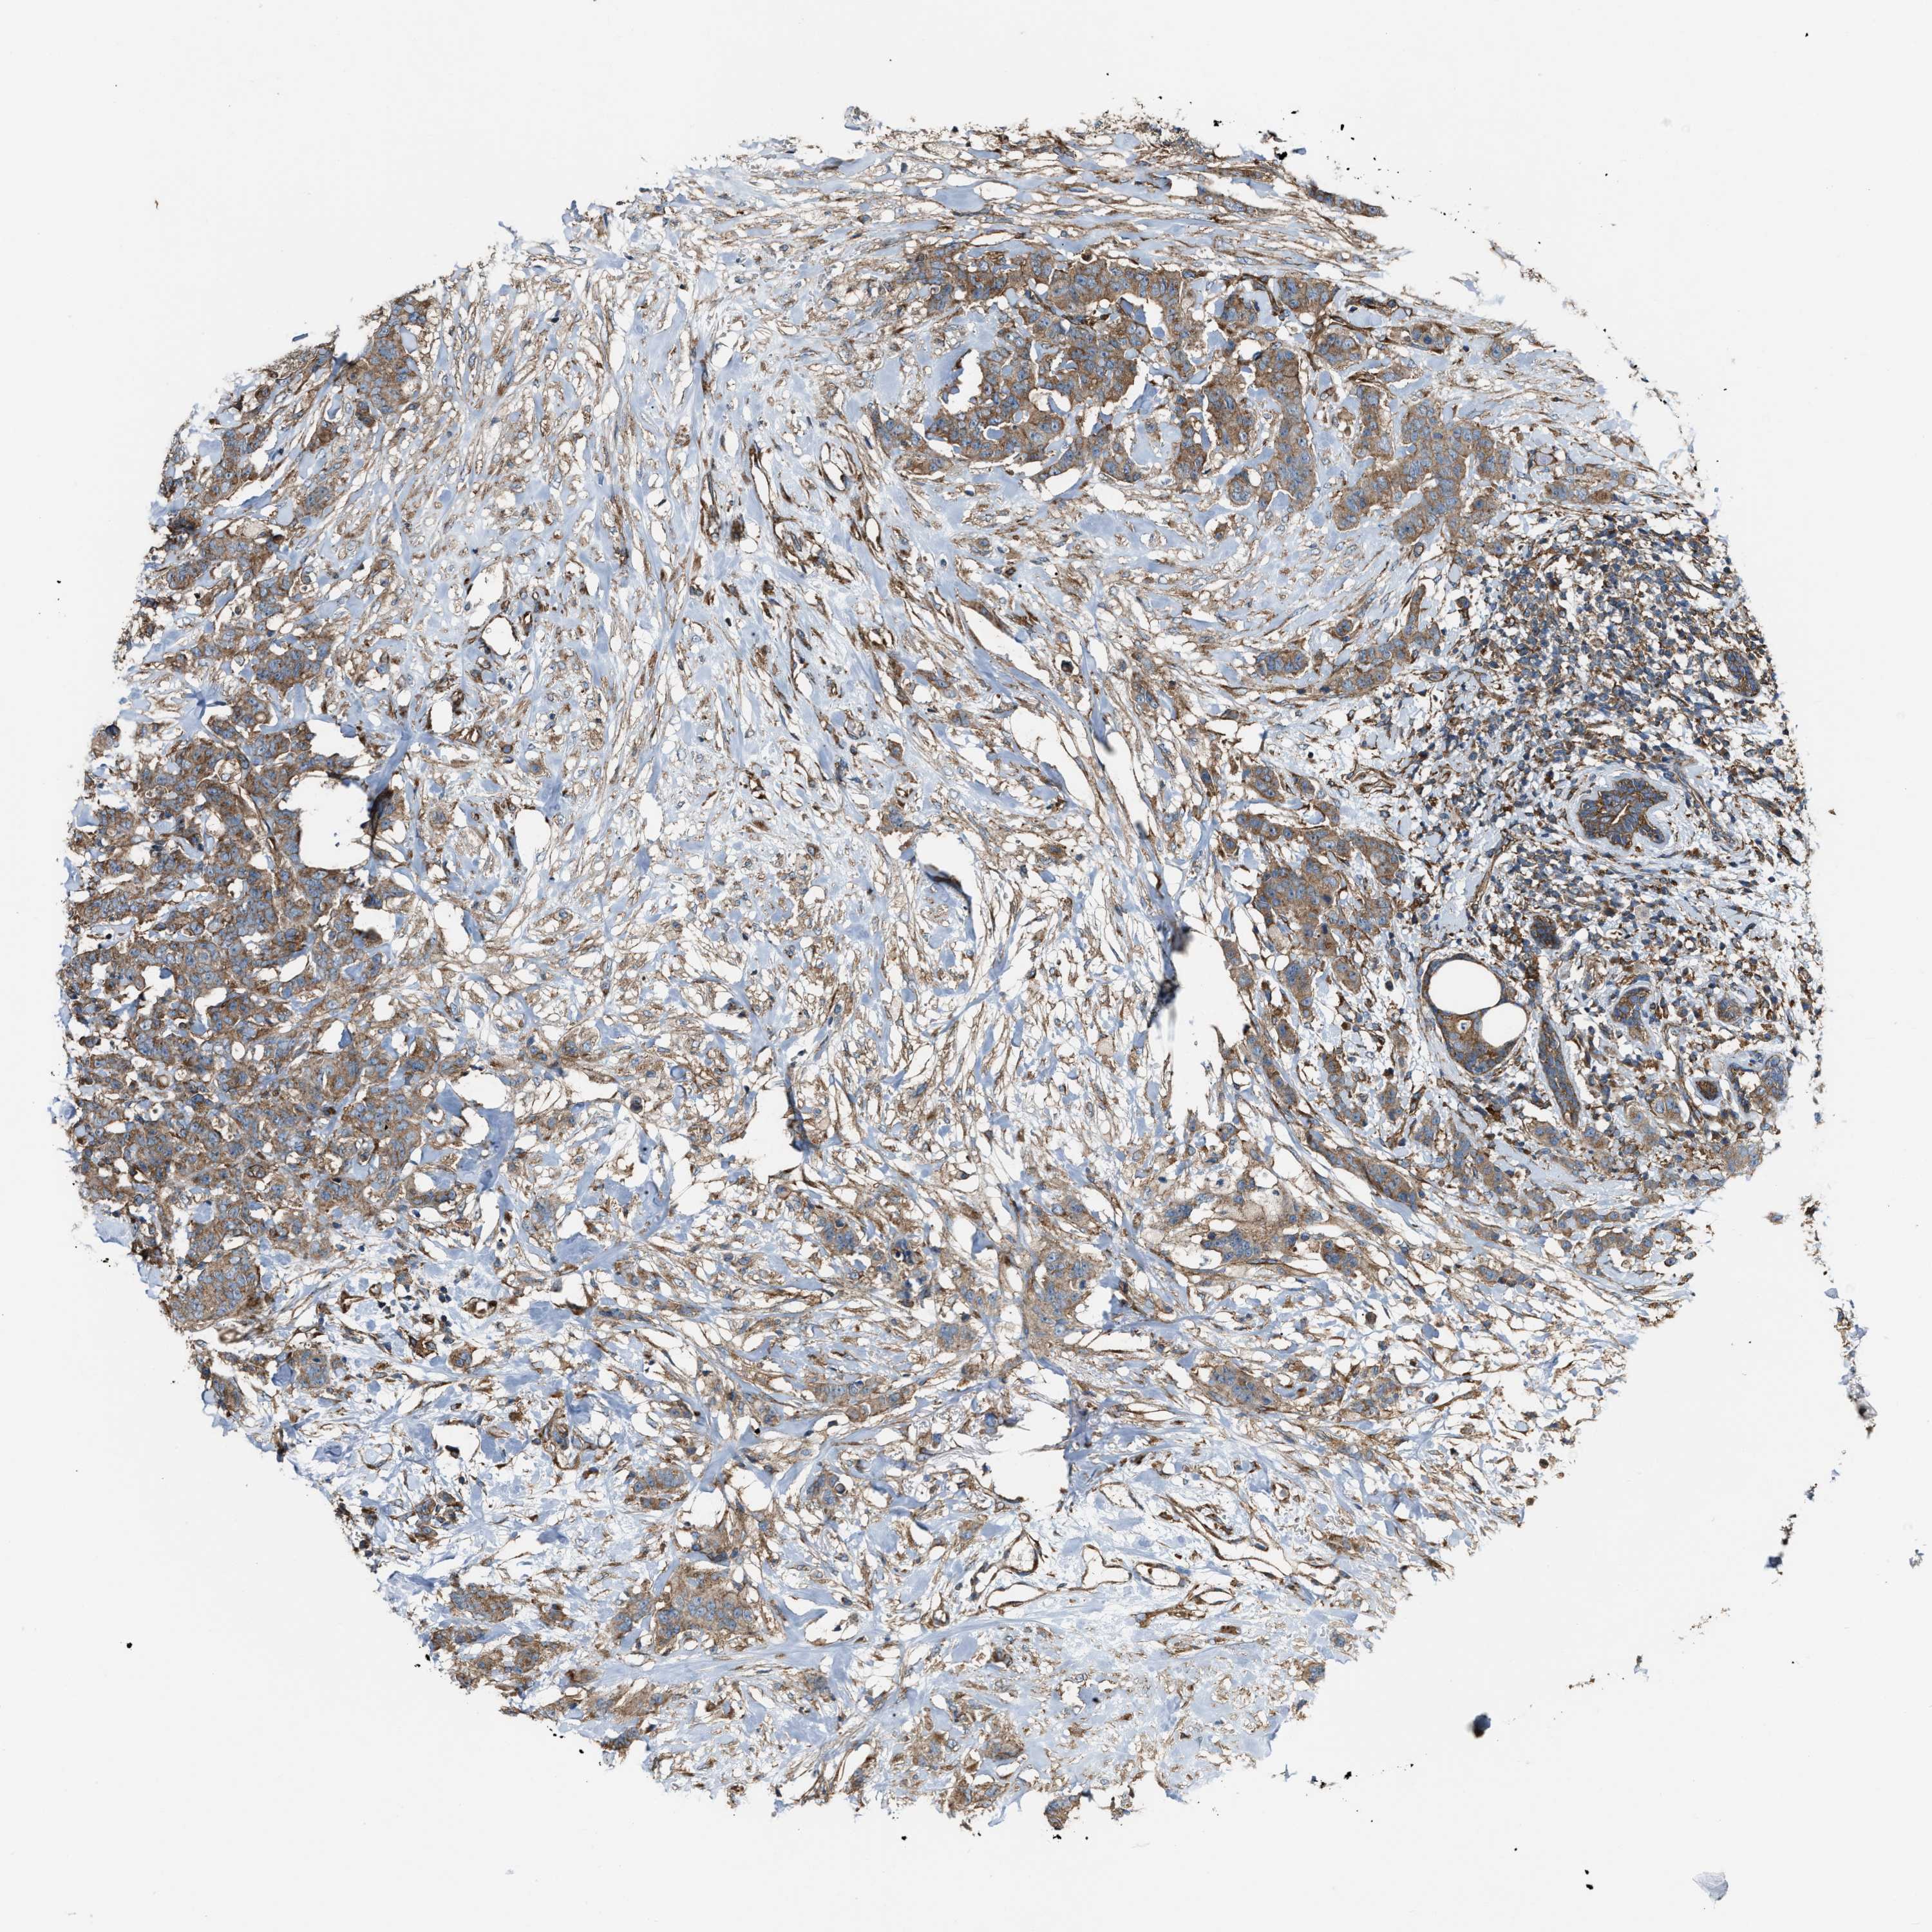

CANCER BREAST CANCER Show tissue menu

BRCA TCGA BRCA VALIDATION PROTEIN EXPRESSION